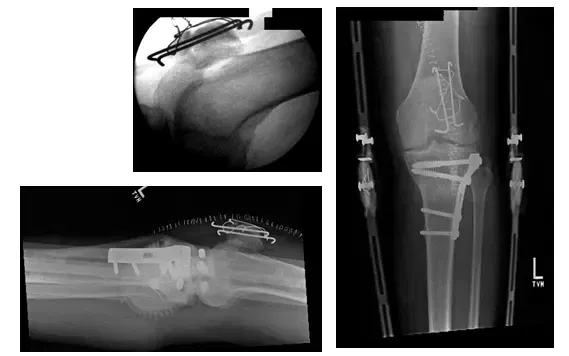

El paciente es un varón de 85 años que se presentó con una prótesis tumoral de rodilla izquierda luxada. El paciente llevaba 3 meses en el postoperatorio de una artroplastia total de rodilla (ATC ) con tumor izquierdo Reconstrucción. El paciente requirió cirugía para...